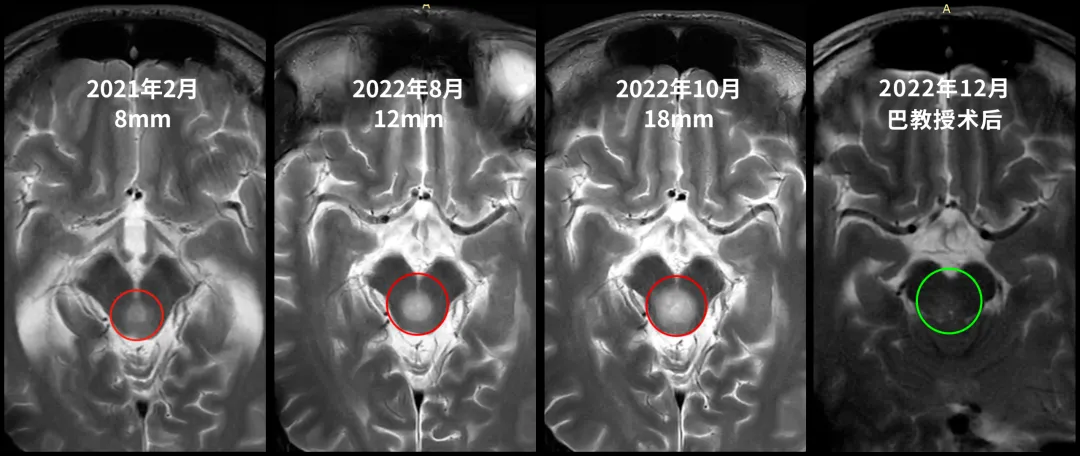

21岁的张远2018年底突然出现剧烈头痛伴呕吐症状。反复头痛已经严重影响到正常的学习和生活,在19年进行了脑脊液分流术,术前磁共振检查提示中脑导水管狭窄,但并未发现占位性病变。分流术后症状消失,张远重新回到校园。2021年2月他再次出现剧烈头痛伴呕吐,并有眼球向上运动困难,调压后症状消失。于当地医院就医检查,提示中脑顶盖占位性病变,最大直径约8mm,随后一年磁共振复查无变化。2022年8月复查磁共振提示肿瘤增大,最大直径12mm。2022年10月复查核磁提示肿瘤增大,自行测量肿瘤大小约18mm,两月内竟激增6mm!迅速增长的肿瘤,让一家人陷入恐慌,必须尽快找到能为孩子安全手术的主刀医生。

2022年12月3日,示范手术顺利完成,巴教授近全切肿瘤,术后无新发后遗症,术后第一天教授查房时,张远意识清醒,能进行交流,术前担心的昏迷、瘫痪真的没有在这个大男孩身上发生。术后一个月病理报告为2级多形性黄色星形细胞瘤,是预后相对较好的肿瘤,手术是延长预后和生存期的治疗方式,而张远的多形性黄色星形细胞瘤位置长在生命中枢-脑干,动刀手术已经实属一大难题,能得到巴教授近全切的效果已是万幸的结果。